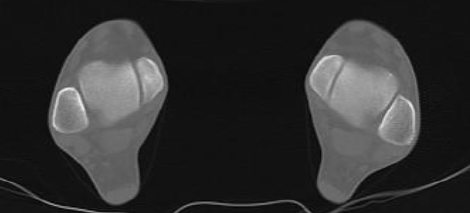

Coupes

F

Malléoles tibiales

G

Grand axe de la rotule